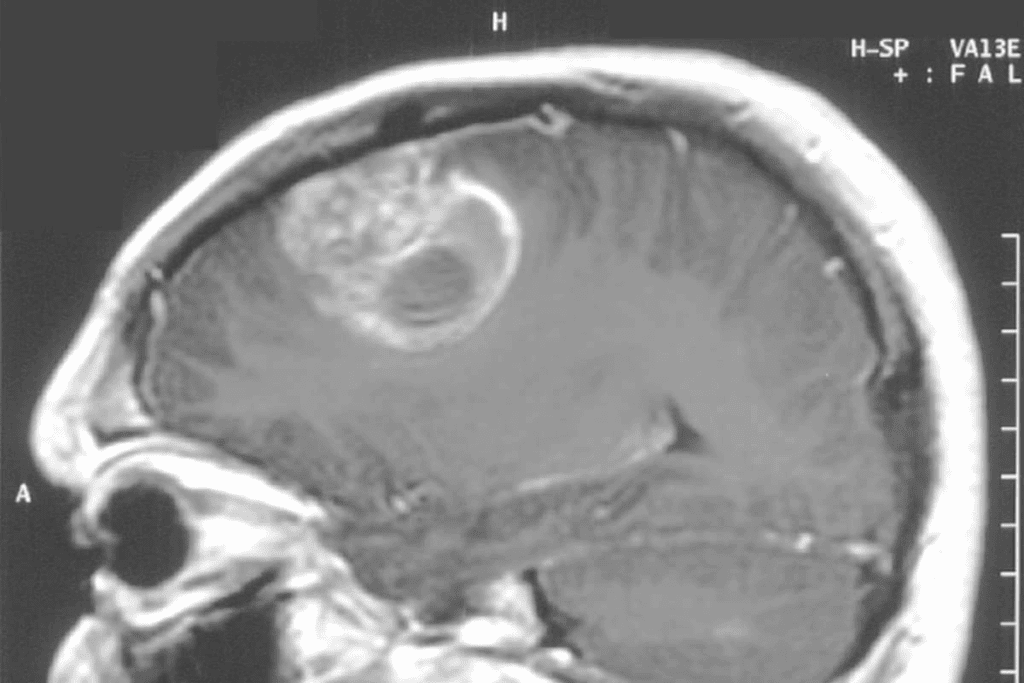

Imaging Studies (MRI, CT Scan)

Imaging tests are key in diagnosing brain tumors. We use Magnetic Resonance Imaging (MRI) and Computed Tomography (CT) scans to see the tumor’s details. MRI is best for soft tissue and is often used for brain tumors.

The benefits of MRI include:

• High-resolution images of soft tissues

• Ability to detect tumors in various brain regions

• Detailed information for surgical planning